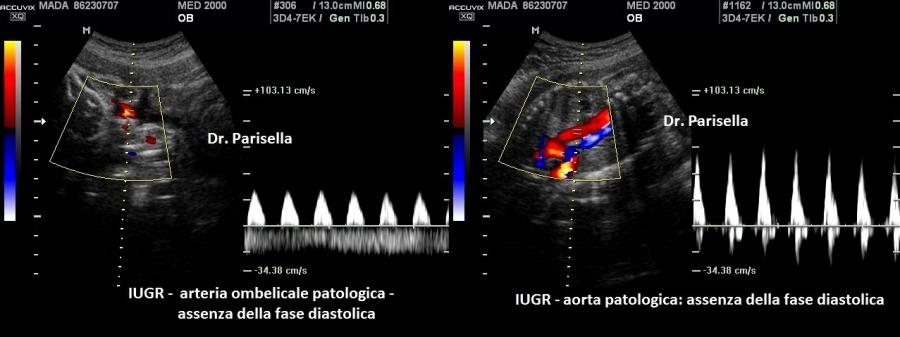

I segni ecografici sono numerosi :

1. IUGR